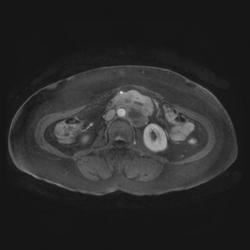

ИП FLAIR Axial